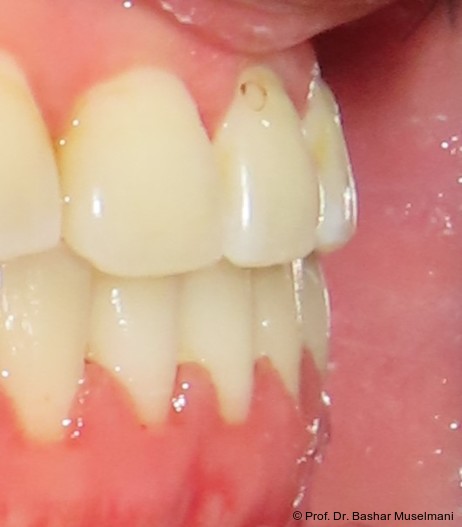

Die Abbildungen 1 bis 3 zeigen die initiale klinische und radiologische Ausgangssituation.

Therapieplanung und Entscheidungsfindung

Aufgrund der skelettalen Ausgangssituation mit einer Klasse III-Dysgnathie im Borderline-­Bereich wurde initial eine kieferorthopädisch-­chirurgische Kombinationsbehandlung in Erwägung gezogen. Unter Berücksichtigung der moderaten sagittalen Diskrepanz, der vorhandenen dentoalveolären Kompensationsmöglichkeiten sowie der Ablehnung eines operativen Eingriffs durch den Patienten wurde jedoch eine rein kieferorthopädische Camou­flage-Be­hand­lung als therapeutische Alternative gewählt.